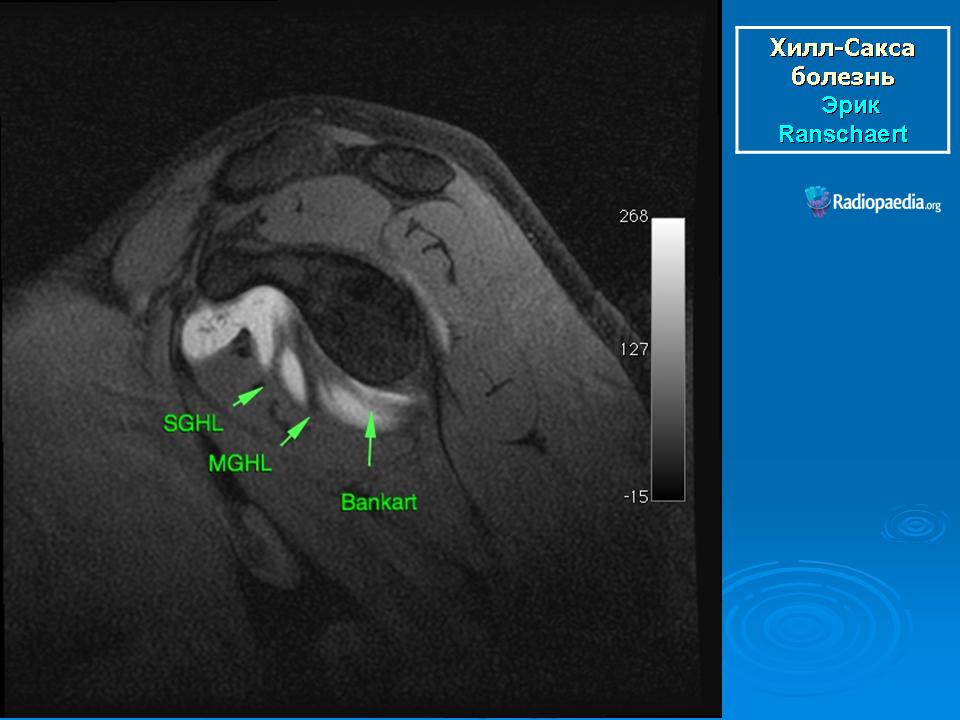

На рентгенограмме плечевого сустава определяется умеренный остеопороз головки плечевой кости. Иногда на ее задненаружной поверхности позади вершины большого бугорка выявляется вдавленный дефект (повреждение Хилл-Сакса). Дефект четко виден на рентгенограмме в аксиальной проекции. Аналогичный, но менее выраженный дефект может быть выявлен в зоне передненаружного края суставной впадины лопатки. Также в диагностике причин привычного вывиха плеча помогает МРТ исследование.